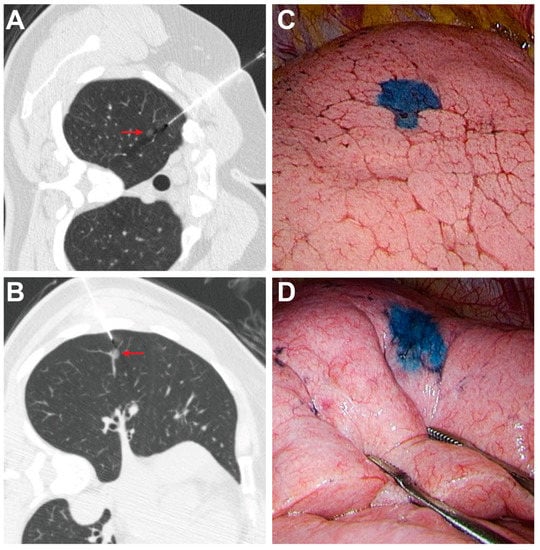

2.2. CT-Guided PBD Localization

2.3. Success Rate and Complications

2.4. VATS after Localization